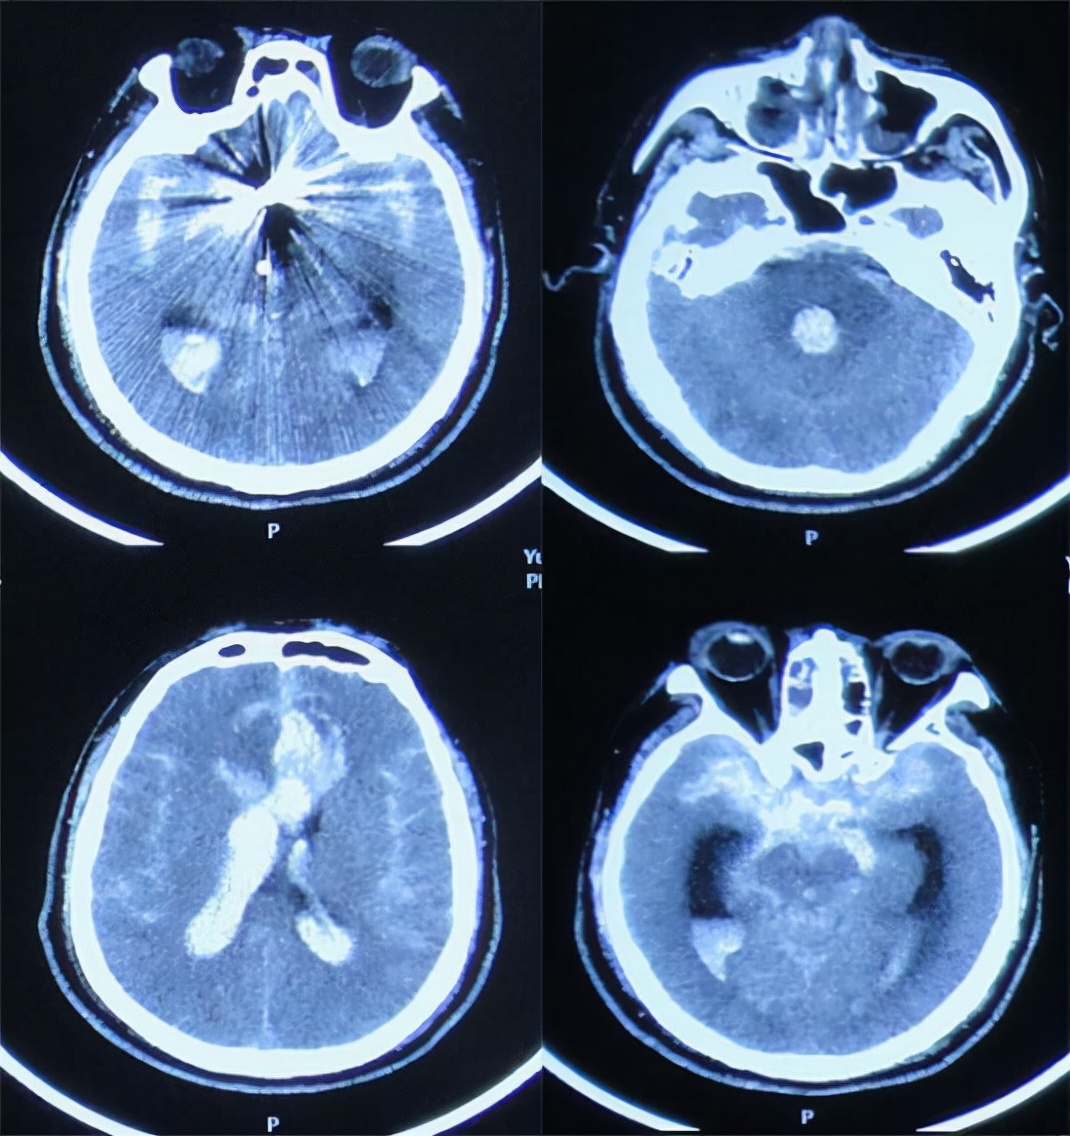

入院第一天(2020年10月17日)23时50分,急诊行动脉瘤栓塞术+右侧脑室外引流术。入院第二天(2021年10月18日),复查头部CT示动脉瘤栓塞+脑室外引流术后,脑室内血肿铸型( 图-3 )。

图-3: 2020年10月18日头部CT

2020年10月20日,10月22日两天复查头部CT示颅内出血逐渐减少(引流)( 图-4、图-5 )但双侧颞角稍有扩张。

图-4: 2020年10月20日头部CT

图-5: 2020年10月22日头部CT